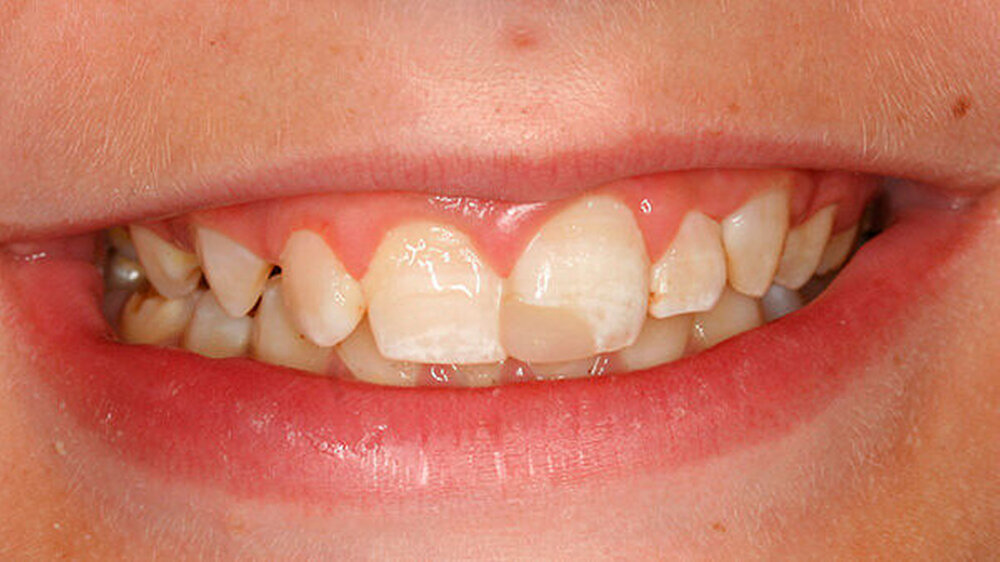

Auf den ersten Blick auffällig waren die Opazitäten der oberen mittleren und seitlichen Inzisivi. Der linien- und teils wolkenförmige Verlauf der Opazitäten der mittleren Inzisivi erschien zunächst dem klinischen Bild einer Fluorose zu entsprechen.

Auch wiesen die lateralen Inzisivi ebenfalls fluoroseähnliche Opazitäten auf, an Zahn 22 war zusätzlich im fluorotischen Bereich eine bräunliche Verfärbung sichtbar (Abbildung 1). Bei genauerer Betrachtung der Frontalansicht sind bukkal im Seitenzahnbereich durchaus schon weitere Schmelz-Opazitäten zu erkennen, die allerdings eher nicht dem Bild einer Dentalfluorose entsprechen (siehe an den Zähnen 14 und 85).